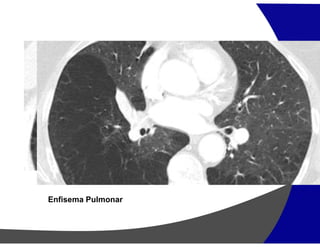

Cistos Áereos – Areas de menor atenuação

Enfisema

Cistos pulmonares (LAM, LIP, Histiocitose de células de Langerhans)

Bronquiectasia

Faveolamento

PADRÃO DE REDUÇÃO DE ATENUAÇÃO

“Manchas pretas”

Parasseptal

Centrolobular Panlobular

Enfisema Pulmonar